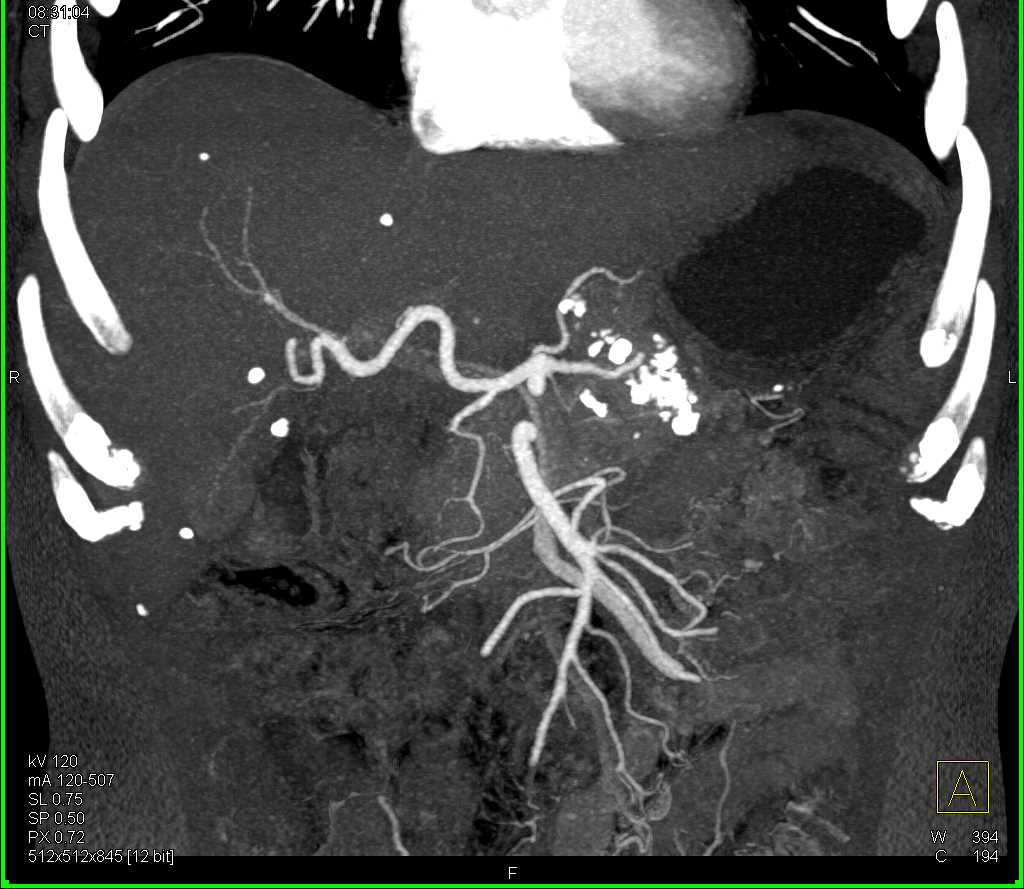

Neuroendocrine Tumor Pancreas